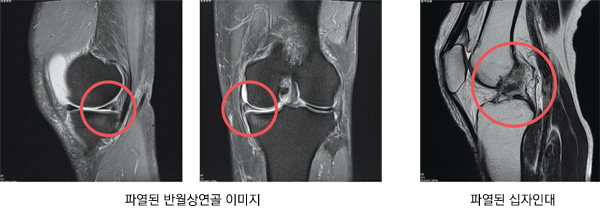

무릎 통증과 부상은 골퍼들 사이에서 흔히 발생하는 부상 중 하나다. 골프보다는 축구나 농구, 테니스와 같은 급격한 방향 전환과 체중이 실리는 운동을 할 때 더 자주 발생하지만, 골프 동작 중에도 무릎에 체중이 실리면 관절이 회전하는 동작이 발생하기 때문에 무릎 부상이 일어나기 쉽다. 특히 우타 골퍼(오른손잡이 골퍼)는 좌측 무릎이 지지대 및 축의 역할을 하기 때문에 과도한 스윙 동작이 반복될 경우 무릎 관절에 회전력과 전단력이 발생하면서 반월상연골 파열이나 전방십자인대 파열과 같은 부상이 나타나게 되는 것이다.

반월상연골판은 대퇴골과 경골 사이에 위치한 반달 모양의 연골 조직을 지칭한다. 무릎의 쿠션 역할을 하여 충 격을 흡 수하고, 무 릎이 자연스럽게 굽혔다 펴질 수 있도록 돕는다.

골프 스윙을 할 때 무릎의 회전력이 반복적으로 발생하고, 연골판이 무릎 위아래 뼈 사이에 끼어 비틀어질 경우, 연골판이 찢어질 수 있다. 찢어진 연골판이 관절 사이에 끼이면 무릎을 제대로 펴지 못하게 되고 통증도 심해진다. 젊은 연령에서도 발생할 수 있으나, 50대가 넘어가면 연골판 조직이 퇴행성으로 약해지며 손상에 취약해져 연골판 파열이 더 자주 발생한다.

반월상연골판이 손상된 상태로 두게 되면 퇴행성관절염을 유발할 수 있다. 퇴행성관절염이 진행되면 주위에 근육 및 중요 구조물이 함께 손상될 가능성이 높다. 때문에 골프 후 무릎 통증이 발생하면 반월상 연골판손상 여부를 빠르게 확인하는 것이 좋다.

전방십자인대는 무릎의 중요 구조물로, 무릎의 안정성을 유지하는 역할을 한다. 파열 시 무릎에서 뚝 소리가 나며 극심한 통증을 느낀다. 전방십자인대가 파열되면 통증과 함께 붓기가 동반되며, 이 경우 대부분 즉시 병원을 방문해야 한다. 전방십자인대의 파열은 무릎의 안정성을 저하시키고 비정상적인 관절운동으로 인해 다른 구조물에 2차적인 손상을 유발한다. 기본적인 치료 방법은 수술적 봉합을 통해 인대를 재건하는 것이다.